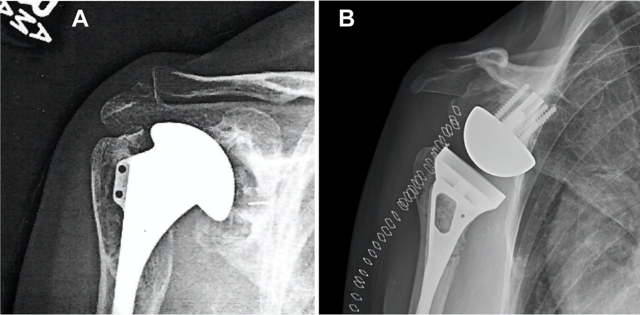

Historical perspective: The injuries shown (see "Gallery" Button - located below text) demonstrate severe fragmentation of the proximal humerus. Prior to the availability of CT imaging to clearly delineate fracture fragments, interpretation relied heavily on surgeon experience to reassemble and stabilize fragments using tools and implants adapted from other anatomic sites.

Today: Modern CT and MRI imaging, along with improved fixation devices such as locked nails and locking plates, have enabled more successful surgical treatments by reducing trauma and improving fracture stability. However, osteoporosis, rehabilitation forces, and delayed bone healing challenge fixation, and failure may occur during early arm use or after a fall. Individualized treatments are often necessary but cumbersome, and insurance considerations may influence operative decisions, as these injuries frequently compromise independent living.

Reverse Total Shoulder Replacement is increasingly used for complex fracture patterns because it can restore painless arm use more reliably in patients with rotator cuff insufficiency. Limitations include reduced overhead motion and risk of dislocation.

Our innovative design restores anatomic mechanics through enhanced glenoid implant fixation. Using patented Patient Match technology, CT data generate implants matched to variable scapular anatomy, providing immediate fixation that counteracts early rehabilitation forces and supports bone ingrowth into a porous surface for permanent fixation. Improved fixation enables mechanical constraint, supports anatomic shoulder replacement designs, improves motion, and reduces dislocation risk.

The proposed solution, Anatomical Rotator Cuff Arthroplasty (ARCA), reflects unprecendented potential to restore normal shoulder biomechanics for patients requiring joint replacement.